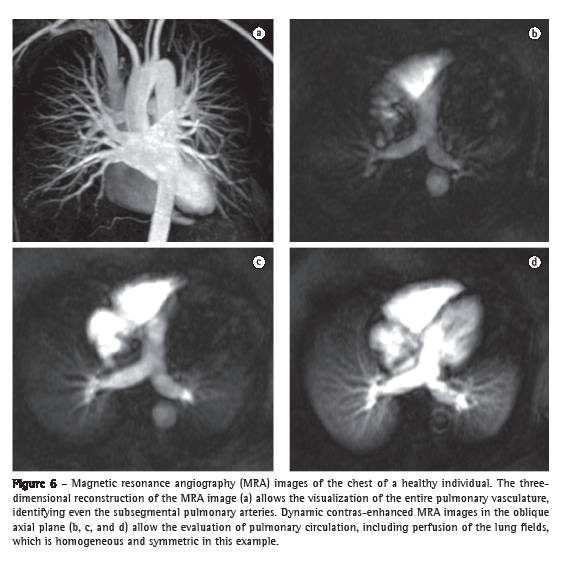

By means of the new MRA techniques, principally the use of gadolinium-enhanced 3D GE sequences, it is now possible to identify even the fourth-order subsegmental pulmonary arteries of a normal lung. This technique allows the acquisition of images of high temporal resolution every 1.0-1.5 s, and these images can also be used to study lung parenchyma perfusion (Figure 6).(40) The GE sequences that show blood flow with high signal intensity, also known as bright blood sequences (balanced GE sequences, cine MRI, and cine phase-contrast MRI) allow the evaluation of the large blood vessels of the thorax without the need for contrast use, as well as allowing the dynamic evaluation of and flow measurement in the pulmonary arteries and aorta, thereby providing functional information for use in morphological studies.(41)

Thromboembolism and pulmonary hypertension